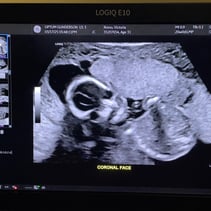

Greetings! I’ve been away from my updates for a couple of weeks, so lets get you caught up on all the things! First off, we had our Anatomy Scan today and hit the half way mark of the pregnancy. WOW. Our baby girl is doing so so well. From head to toe, she’s about 9-10inches and weighs 12oz. A week or two ago I stopped having all pregnancy symptoms besides the obvious physical changes. This was awesome but also made me a little uneasy. I also have not felt much movement and waiting 4 weeks for my 20 week appointment was starting to make me very antsy in a horribly, anxious way. Having a miscarriage the first time around has really made it difficult to relax and feel confident that everything is going well. Last week Steven went ahead and bought me a Doppler to listen to our baby’s heart beat at home while we waited for our next appointment. Once it came in and I found that wonderful sound of her heart, whew! Instant relief. Today was even better! Not only is SHE healthy, but so am I! I started going to the gym a few days out of the week and signed myself up for a 4 week Prenatal Yoga class that takes place every Saturday. My blood pressure today was 118/72 and weighing 129 which is 4 pounds more than my last appointment. I feel wonderful and even more excited than I was before to meet our girl! We’ve started clearing out the room that will be her nursery and are so grateful to the friends and family that have already started pouring their love into us and our baby with the registry gifts! Steven also surprised me with setting me up to visit family in Texas next month during my Spring Break from work. What a guy. 💕 I hope you all enjoy these photos! You‘ll see her profile with her cute little nose! There’s one of her foot, one of her crunched up with her legs bent, a crazy one of her that looks like a Halloween photo, and it’s hard to tell but one of her lips and nose. She was spinning and drinking and kissing us while she was having her first photoshoot. I will start feeling her more in the next couple of months. I have an anterior placenta so it makes things a little harder to feel since its placed in the front of my uterus. She is having fun, nonetheless. That’s all for now! We love you aaalllllll. A note from Steven: we could clearly tell during the sonogram that she gets her dance moves from her daddy.